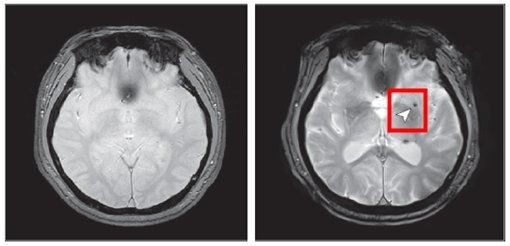

뇌 미세출혈은 뇌 속의 작은 혈관이 손상되어 출혈이 발생하는 것으로, 뇌졸중 등 심각한 뇌혈관 질환의 주요 위험요인으로 알려져 있다.

연구 결과, 중등도 이상의 폐쇄성 수면무호흡증을 가진 사람은 수면무호흡증이 없는 사람에 비해 뇌 미세출혈이 발생할 위험이 약 2배 증가하는 것으로 나타났다. 반면, 경증 수면무호흡증에서는 위험 증가가 관찰되지 않았다.